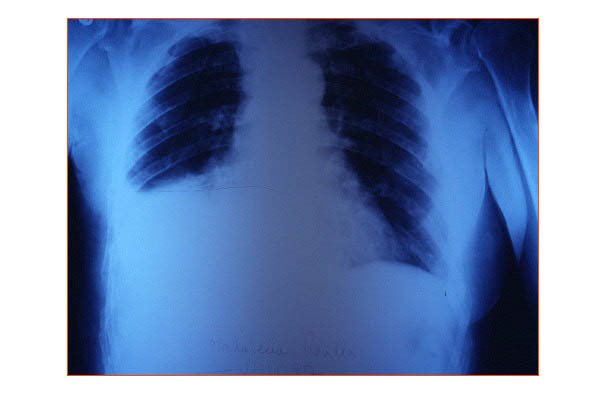

Fibrosis pulmonar. ICC.